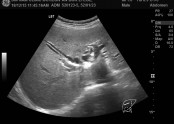

• 소리 없이 찾아오는 침묵의 암이라 불리는 담도암, 담관암

• 담도암은 국내 10대 암에 속하는 암입니다.당남과 담도암 발생 건수에서 남녀를 합친 연령대별로 살펴보면 70대가 36.3%로 가장 많았고, 60대가 24.7% 80대 이상이 24.1% 순으로 결과적으로 나이가 들면서 발생하는 암입니다.담도암이 발생하는 명확한 원인은 참…